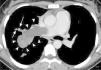

Computed tomography (CT) and magnetic resonance imaging (MRI) are considered to be the most useful tools for differentiation between a tumor and a thrombus.2,3 Both diseases appear as low-attenuation intraluminal filling defects on contrast-enhanced CT, and radiologic differentiation between PA tumor and PA thromboembolism can be difficult.4 CT findings indicative of PA tumor (Fig. 1) include hypodense filling defect with inhomogeneous attenuation occupying the entire lumen of the artery, with an increase in diameter of the involved vessel; contiguous soft tissue-filled PAs with occupation of the entire lumen; vascular distention from tumor growth; beaded peripheral PA; extravascular extension of the thrombus; and patchy and delayed contrast uptake on CT angiography.2,4

Axial contrast-enhanced chest computed tomography of a 35-year-old woman with dyspnea, chest pain, and hemoptysis over several months. An extensive irregular filling defect with inhomogeneous attenuation occupies the right main pulmonary artery and extends into the pulmonary artery branches, with increased vascular diameters (arrowheads). Note also the beaded aspect of a peripheral artery (arrows).